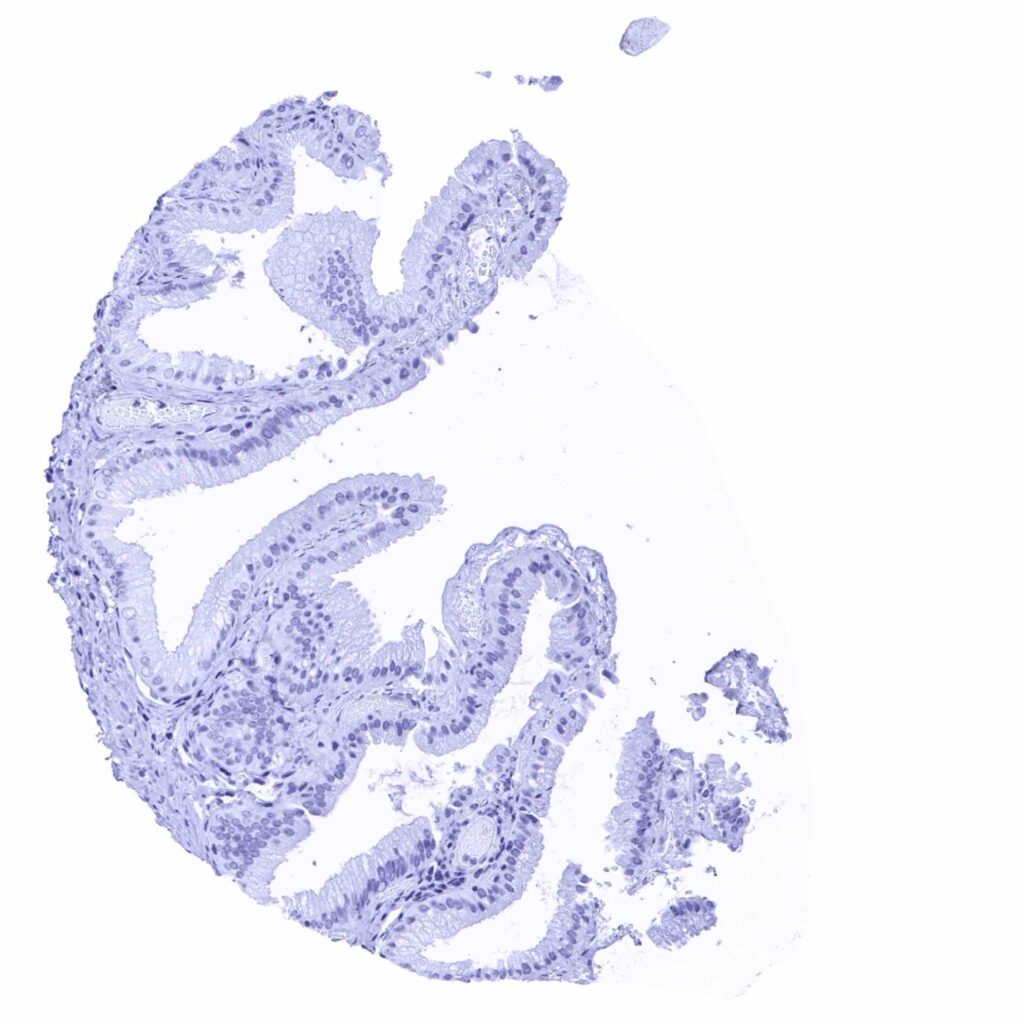

Stomach, antrum – Granular cytoplasmic prostein staining of moderate intensity in surface epithelial cells (prostein immunohistochemistry)

Stomach, corpus – Granular cytoplasmic prostein staining of moderate intensity in surface epithelial cells (prostein immunohistochemistry)